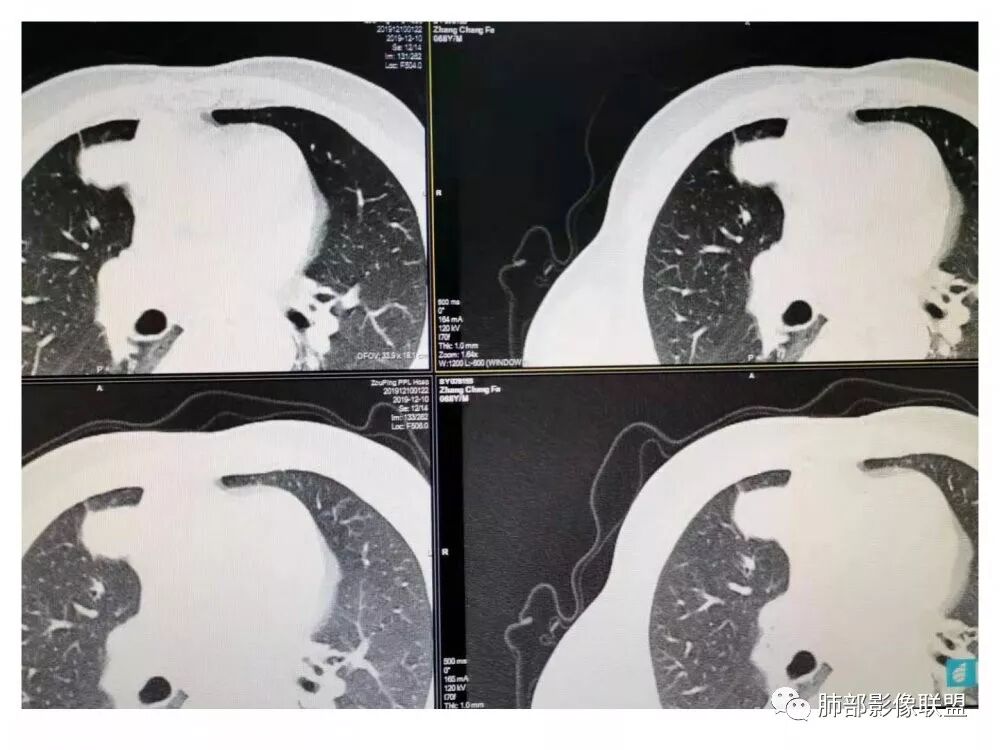

胸部CT:右肺中叶内侧段紧邻心脏实性结节,边缘光滑,边界清楚,宽基底与胸膜相连,内可见不规则钙化,钙化内见点状低密度影,增强中度强化,综合考虑良性病变。畸胎瘤可能大,鉴别胸膜孤立性纤维瘤及胸腺瘤。

王秀仙:右侧前纵隔肿块,边缘分叶,周围肺组织推移,宽基底与纵隔胸膜相连,可见胸膜尾征,密度不均,病灶中心可见斑块状钙化,右侧内乳动脉位于病灶前外侧并略增粗,实性成分明显强化,考虑纵隔畸胎瘤,鉴别胸腺瘤。

肺侧表面光滑,血管推移

胸膜增厚,朝肺侧稍掀起。

支持肺外